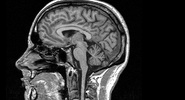

SA: ученые нашли белок, который ведет к омоложению стареющих клеток мозга

С возрастом нейрональные стволовые клетки утрачивают способность к активному размножению, что приводит к уменьшению нейрогенеза и ухудшению когнитивных процессов.Ридус